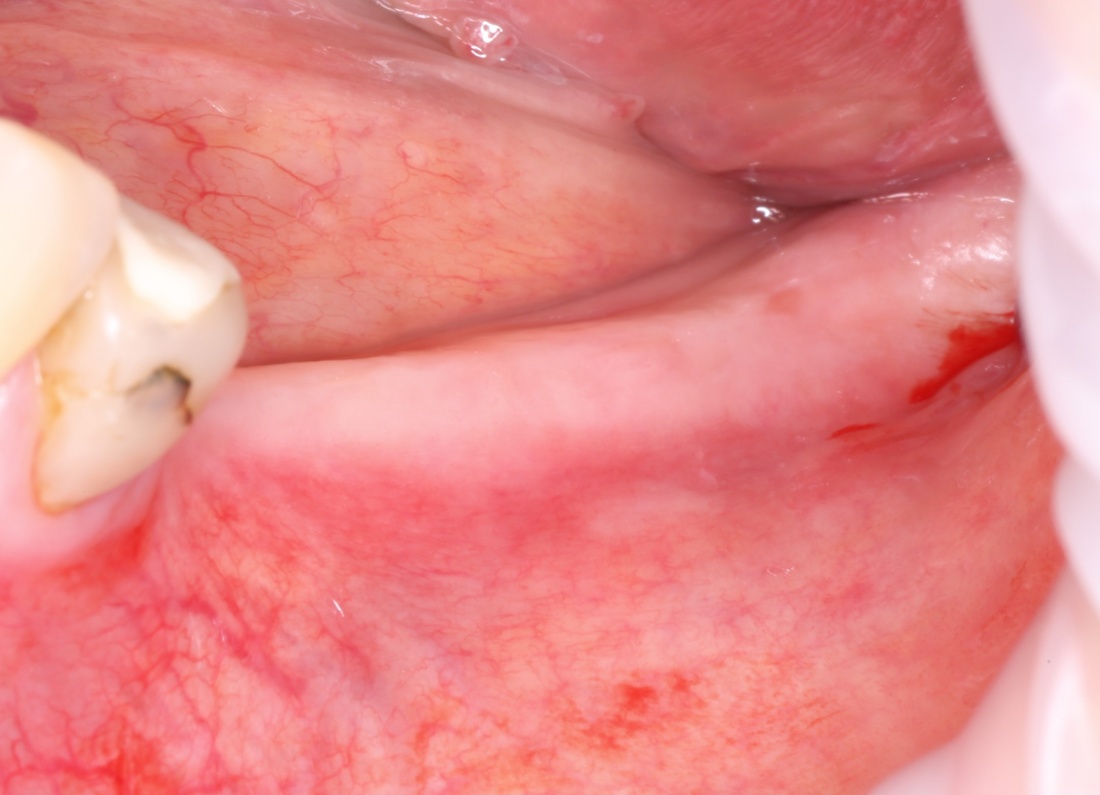

Забор костного фрагмента проводится с наружной косой линии с помощью ультразвукового пьезохирургического инструмента. Ничего сверхнового и супернеобычного тут нет, совершенно стандартная методика. С той лишь разницей, что молоток для этого используют только фашисты и только в гестапо использовать не нужно, всё делается усилием и ловкостью рук.